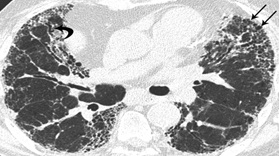

High Resolution CT of the lungs revealed diffuse areas of sub pleural reticulation bilaterally, with no specific predilection for any zone. Patchy areas of ground glass attenuation were noted throughout both the lungs. No evidence of traction bronchiectasis or subpleural cyst formation was seen. These features were suggestive of early (Grade1) pulmonary fibrosis [Table/Fig-4].

CT Lung showing features suggestive of Grade 1 Pulmonary Fibrosis(black arrows)